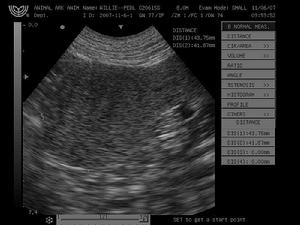

脾良性腫瘤——檢查腹部X線檢查,可發現脾影增大及局部壓迫徵象,但不具特異性胃底及大彎部於鋇餐後見有壓跡橫結腸脾曲於鋇灌腸後可見被推向右方左側腎臟在靜脈造影下可見被推向下方B超檢查可作為脾臟腫瘤的首選檢查能顯示脾臟大小、區分腫瘤的囊實性、了解腫瘤的包膜情況對脾臟腫瘤的診斷有很高價值。彩色都卜勒超聲檢查可了解腫瘤內部的血供情況有助於判斷腫瘤的性質。CT是診斷脾臟腫瘤最有價值的影像學檢查能比較準確提供腫瘤的大小、形態與周圍臟器的關係,能發現約1cm左右的小腫瘤;還可比較詳細了解周圍臟器有無其他病變等MRI對脾臟腫瘤的診斷價值與CT相似臨床套用尚不多選擇性腹腔動脈造影可了解脾臟血管分支的分布情況可根據腫瘤血管的多寡、壓迫、中斷和新生血管等來判斷其性質,對脾臟腫瘤的診斷與鑑別診斷具有重要價值。